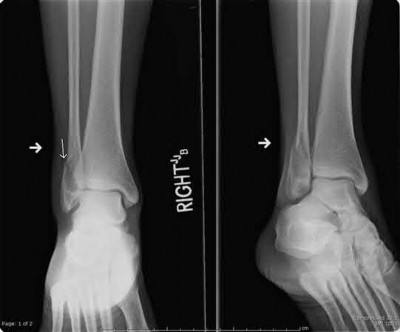

A 25-year-old male sustains an ankle fracture dislocation and undergoes open reduction and internal fixation. He returns to clinic five months following surgery complaining of continued ankle pain and instability with weight bearing. His immediate post-operative AP radiograph is seen in Figure A. Which of the following could have prevented this patient from developing persistent pain?

The patient presents with continued ankle pain and instability following open reduction and internal fixation. The radiograph in figure A demonstrates inadequate restoration of fibular length, likely leading to continued tibiotalar instability.

Illustration A demonstrates fibular malreduction with dislocation of the fibula anterior to the tibial incisura. Illustration B shows a comminuted fibula fracture along with a measurement of length from an intact fibula. The arc from the lateral process of the talus to the peroneal groove of the distal fibula is known as the "dime" sign and should remain unbroken if fibular length has been restored. Illustration C demonstrates the use of a push-pull screw and lamina spreader to regain length intraoperatively for a comminuted fibula fracture.